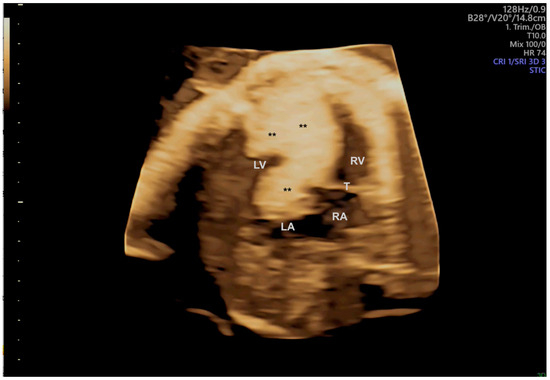

- Pires, G.D.V.; Nieblas, C.O.; Bravo-Valenzuela, N.J.; Araujo Júnior, E.; Castro, P.T.; Werner, H. Ebstein anomaly: 3D virtual and physical models from obstetrical ultrasound data. Echocardiography 2024, 41, e15806. [Google Scholar] [CrossRef] [PubMed]